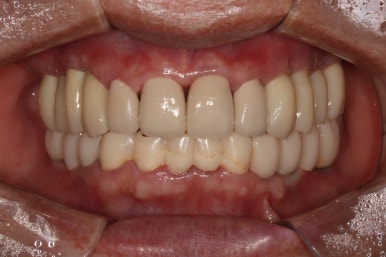

그렇게 완성된 최종 보철물 형태입니다.

임시치아와 다르게 지르코니아 크라운으로 제작되어 훨씬 단단하고 매끈하고 이상적인 형태를 가진걸 보실 수 있으실거에요.

위 아래 앞니 모두 적절한 길이로 회복이 되었고, 어금니도 이상적인 형태를 보여주고 있습니다.

제거가 덜 된 접착제가 조금 보이긴 하지만,

좌우로 옆에서 봤을 때도 충분히 기능이 잘 되게끔 잘 물리는 어금니를 보실 수 있을거에요.

식사 시 음식이 덜 끼도록 치아와 치아사이를 최대한 닫아놓은 모양입니다.

위아래 모두 아주 이상적인 형태로 제작된 치아모양의 지르코니아 크라운을 보실 수 있을거에요.

이 정도면 전체 구강 재건 (full arch rehabilitation)이라고 불러야 합니다.

상당히 난이도가 있는 케이스이며, 완성후에 자연스럽게 사용하시게 되려면 정말 경험 많은 치과의사가 필요합니다. 이를 위해 보철과 전문의와의 협진은 상당히 좋은 시너지를 내죠.

솔직히 제가 봐도 미라클한 최종 치료 사진...

이렇게 잘해도 되는건가요..!!!

적절한 색조와 형태를 가진 앞니 보철물.. 그리고 적절히 기능하도록 설정된 아래턱의 위치

모든것이 조화롭게 완성된 치료 후 구강내 사진입니다.

환자분도 정말 너무너무 대만족 하셨어요 :)